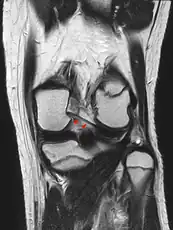

Posterior meniscofemoral ligament on MRI, coronal

The Posterior meniscofemoral ligament (also known as the ligament of Wrisberg) is a small fibrous band of the knee joint. It attaches to the posterior area of the lateral meniscus and crosses superiorly and medially behind the posterior cruciate ligament to attach to the medial condyle of the femur.[1]

The posterior meniscofemoral ligament is found in 64.4% of the subjects in MRI scan of the knee.[1]